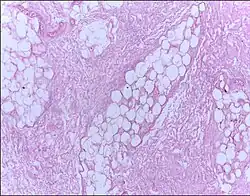

![]() |

Fat necrosis | Breast lump showing an area of fat necrosis showing shadowy outlines of necrotic adipocytes surrounded by an inflammatory reaction with cholesterol clefts. | Category: Histopathology of liponecrosis | Liponecrosis |